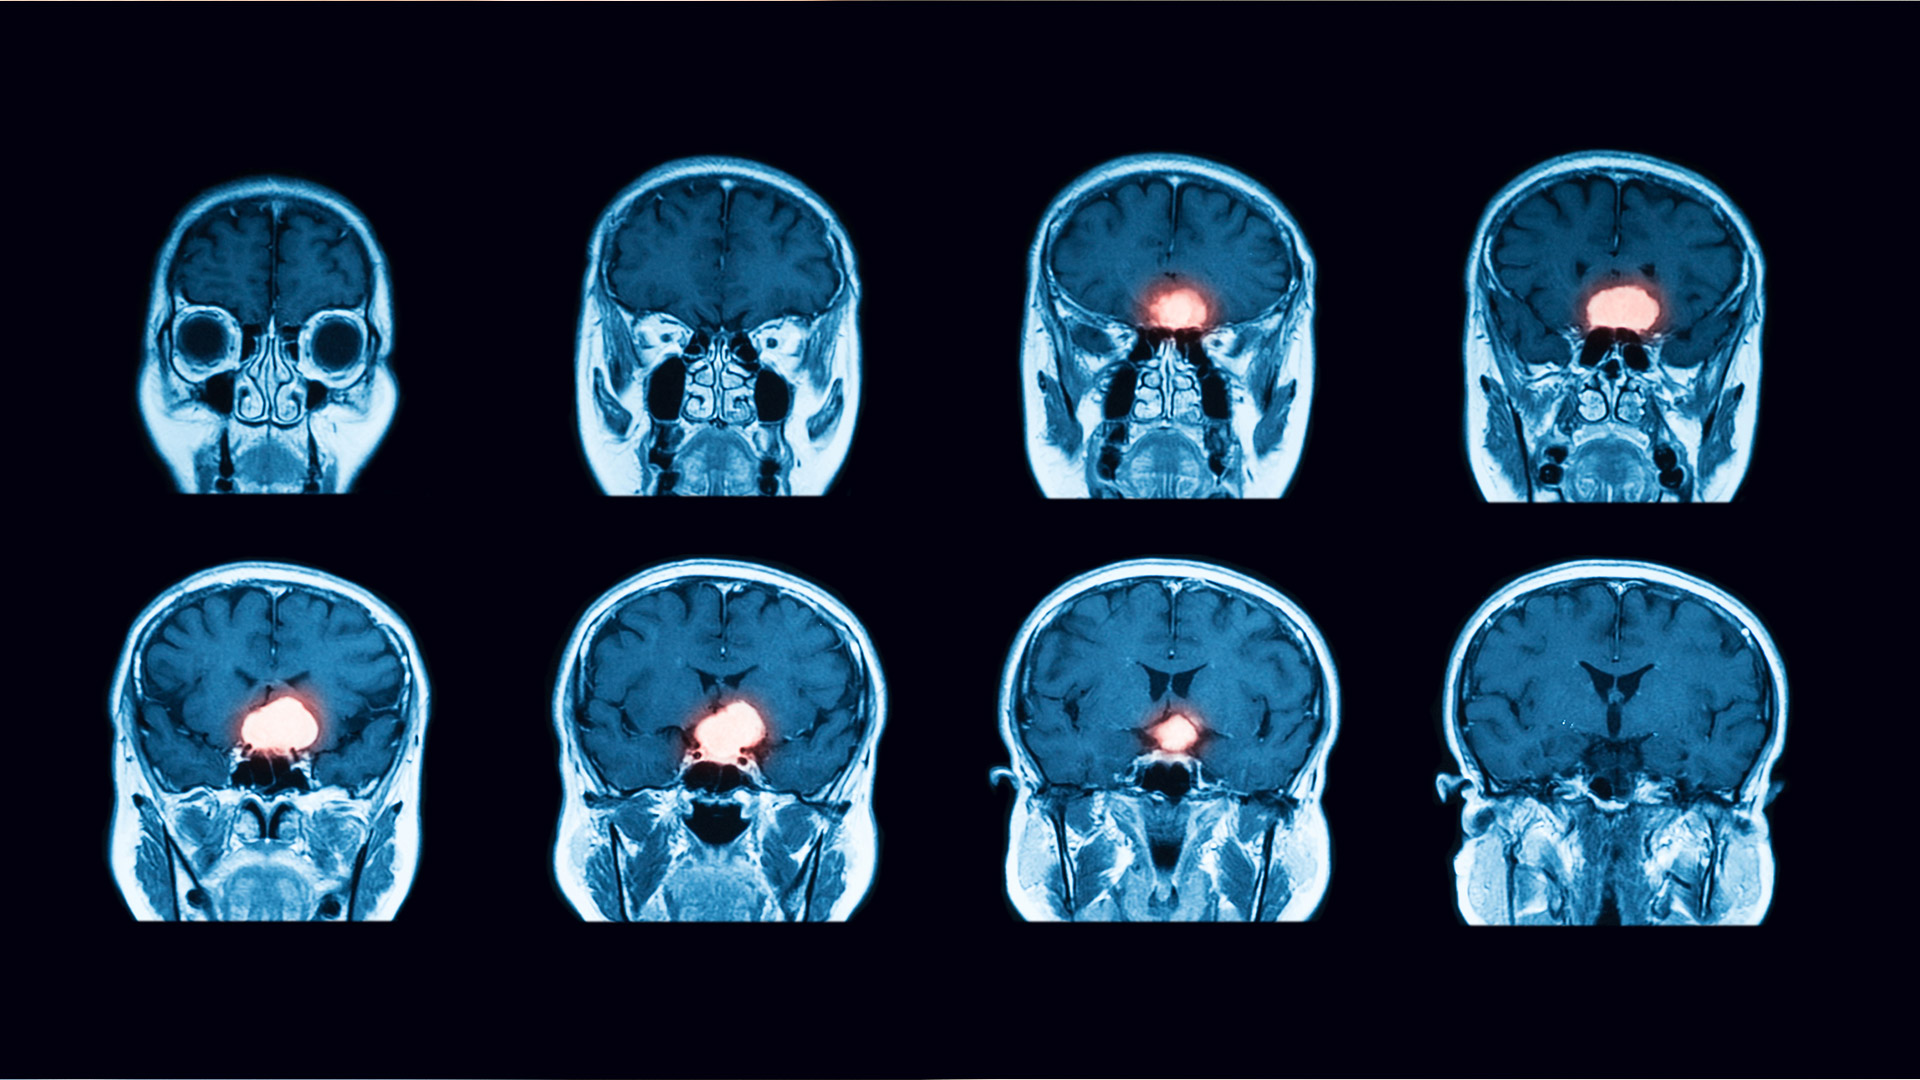

¿Qué son los Adenomas Hipofisiarios?

Los adenomas hipofisiarios son tumores de la hipófisis, una glándula pequeña en la base del cerebro que regula funciones hormonales esenciales.

Aunque la mayoría son benignos, pueden afectar la visión, el equilibrio hormonal y la calidad de vida. Ofrecemos una valoración integral para definir el tratamiento más adecuado: desde seguimiento especializado hasta cirugía de mínima invasión.

Vigilancia estrecha con resonancias periódicas para tumores pequeños y asintomáticos.